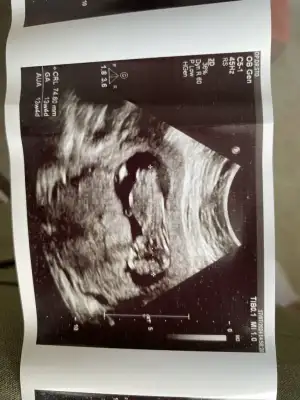

Kızlar öncelikle sağlıkla gelsin bebişlerimiz. Ben cinsiyetle alakalı bir şey sormak istiyorum. Baştan beri kız hissediyorum ilk bebegim ve 3 kez rüyamda kız gördüm. Hatta üçüncüsü çok netti suratını bile çizebilirim. Ama iki doktora gittim ikisi de erkek dedi 13-14. Haftada falandık sanırım. Şuan 16 olmak üzere. Acaba yanılma ihtimalleri var mı ben hala kız oldugunu hissediyorum rüyalardan dolayı kafam çok karışık.

Yanılma olabilir canım ben 12 haftada Medical park Keçiören hastanesinde çok iyi bi doktora gittim ve kesin erkek dediler ama ben hep kız hissediyorum hiç inanmadım 15.ve 17 haftada devlet hastanesine gittim ve bu bebek kız dediler kesinleşti kız olduğu Allah gönlüne göre versin inşallah